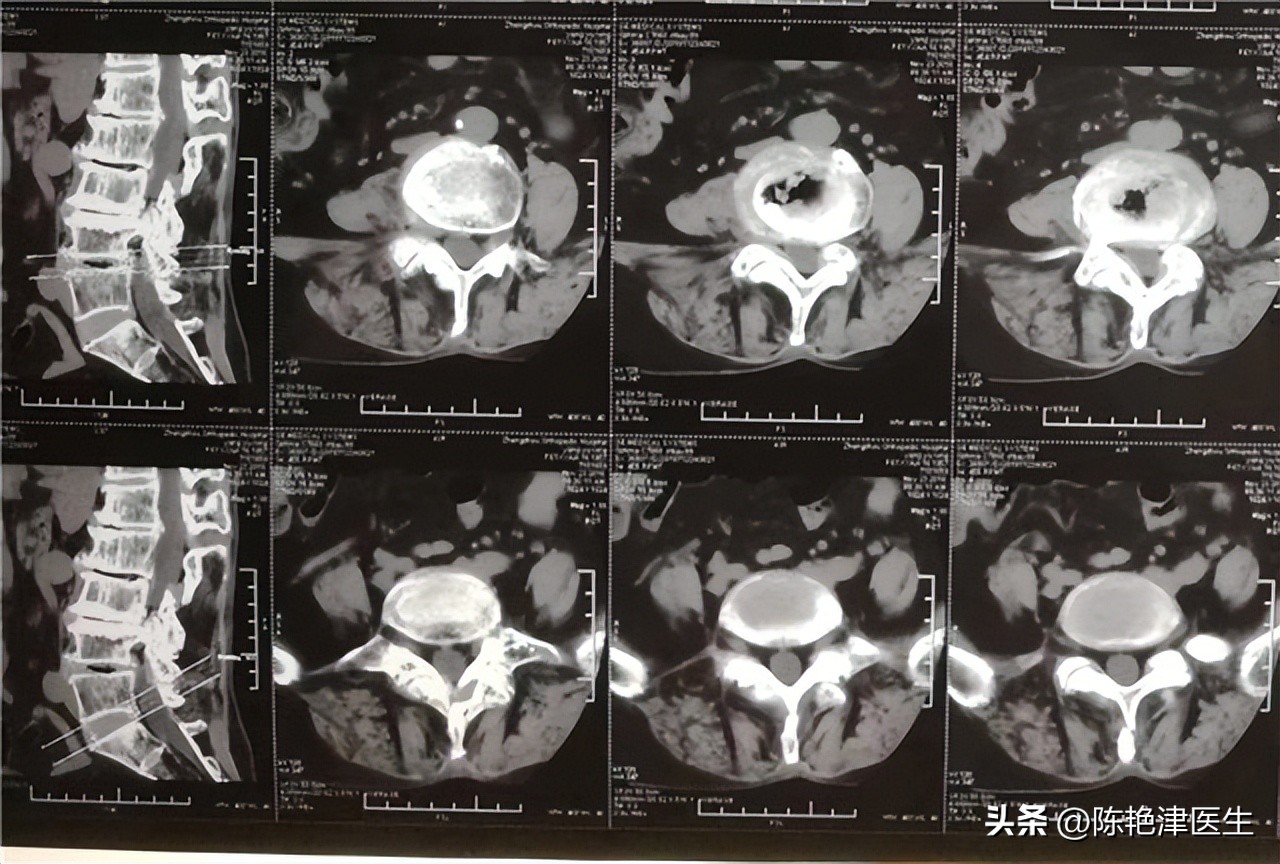

了解李叔情况后,随即为李叔进行腰椎X线检查,检查结果发现李叔腰椎骨质被破坏,腰椎骨质发生病变,通过腰椎CT发现腰椎旁出现病灶,疑似肿瘤病灶, 行穿刺活检提取腰椎病灶,活检发现透明细胞癌,透明细胞癌主要位于肾小管上皮细胞 ,以上检查说明 李叔可能发生了肾癌 ;通过尿常规发现李叔血红细胞数量增多,尿液颜色正常,因此 确定李叔发生了镜下血尿。

行腹部超声检查发现肾小管附近出现块状阴影,通过肾区平扫CT发现低密度圆形和椭圆形肿块, CT检查使用造影剂时出现典型的“快进快出”表现,影像检查中出现这一现象常提醒肿瘤发生。

CT检查发现李叔静脉系统受侵,肾区淋巴结出现部分转移,肾脏邻近器官无转移,但出现了腰椎转移,确定李叔癌细胞出现了骨转移, 最终确诊李叔为中晚期肾癌。